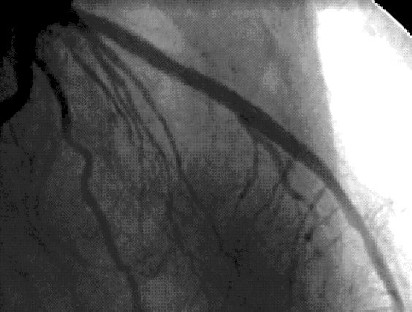

Caso C-3

Coronariografía

Se demuestra lesión larga de arteria descendente anterior, sin otras lesiones significativas. Se decide implante de stent.